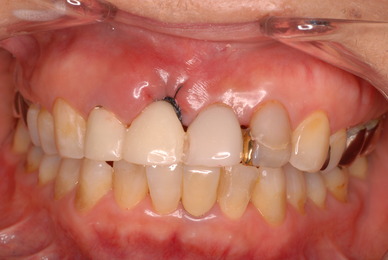

現実を見ればお口の中には“異物”である金歯、銀歯、セラミック、インプラントのオンパレードです。

必ずばい菌が侵入しないようにしてばい菌である虫歯を除去します。

銀歯の下はばい菌だらけです。こういうのはよくあります。取り残しですね。![treatment_05[1]](https://livedoor.blogimg.jp/netdental/imgs/3/a/3ad019d0-s.jpg)